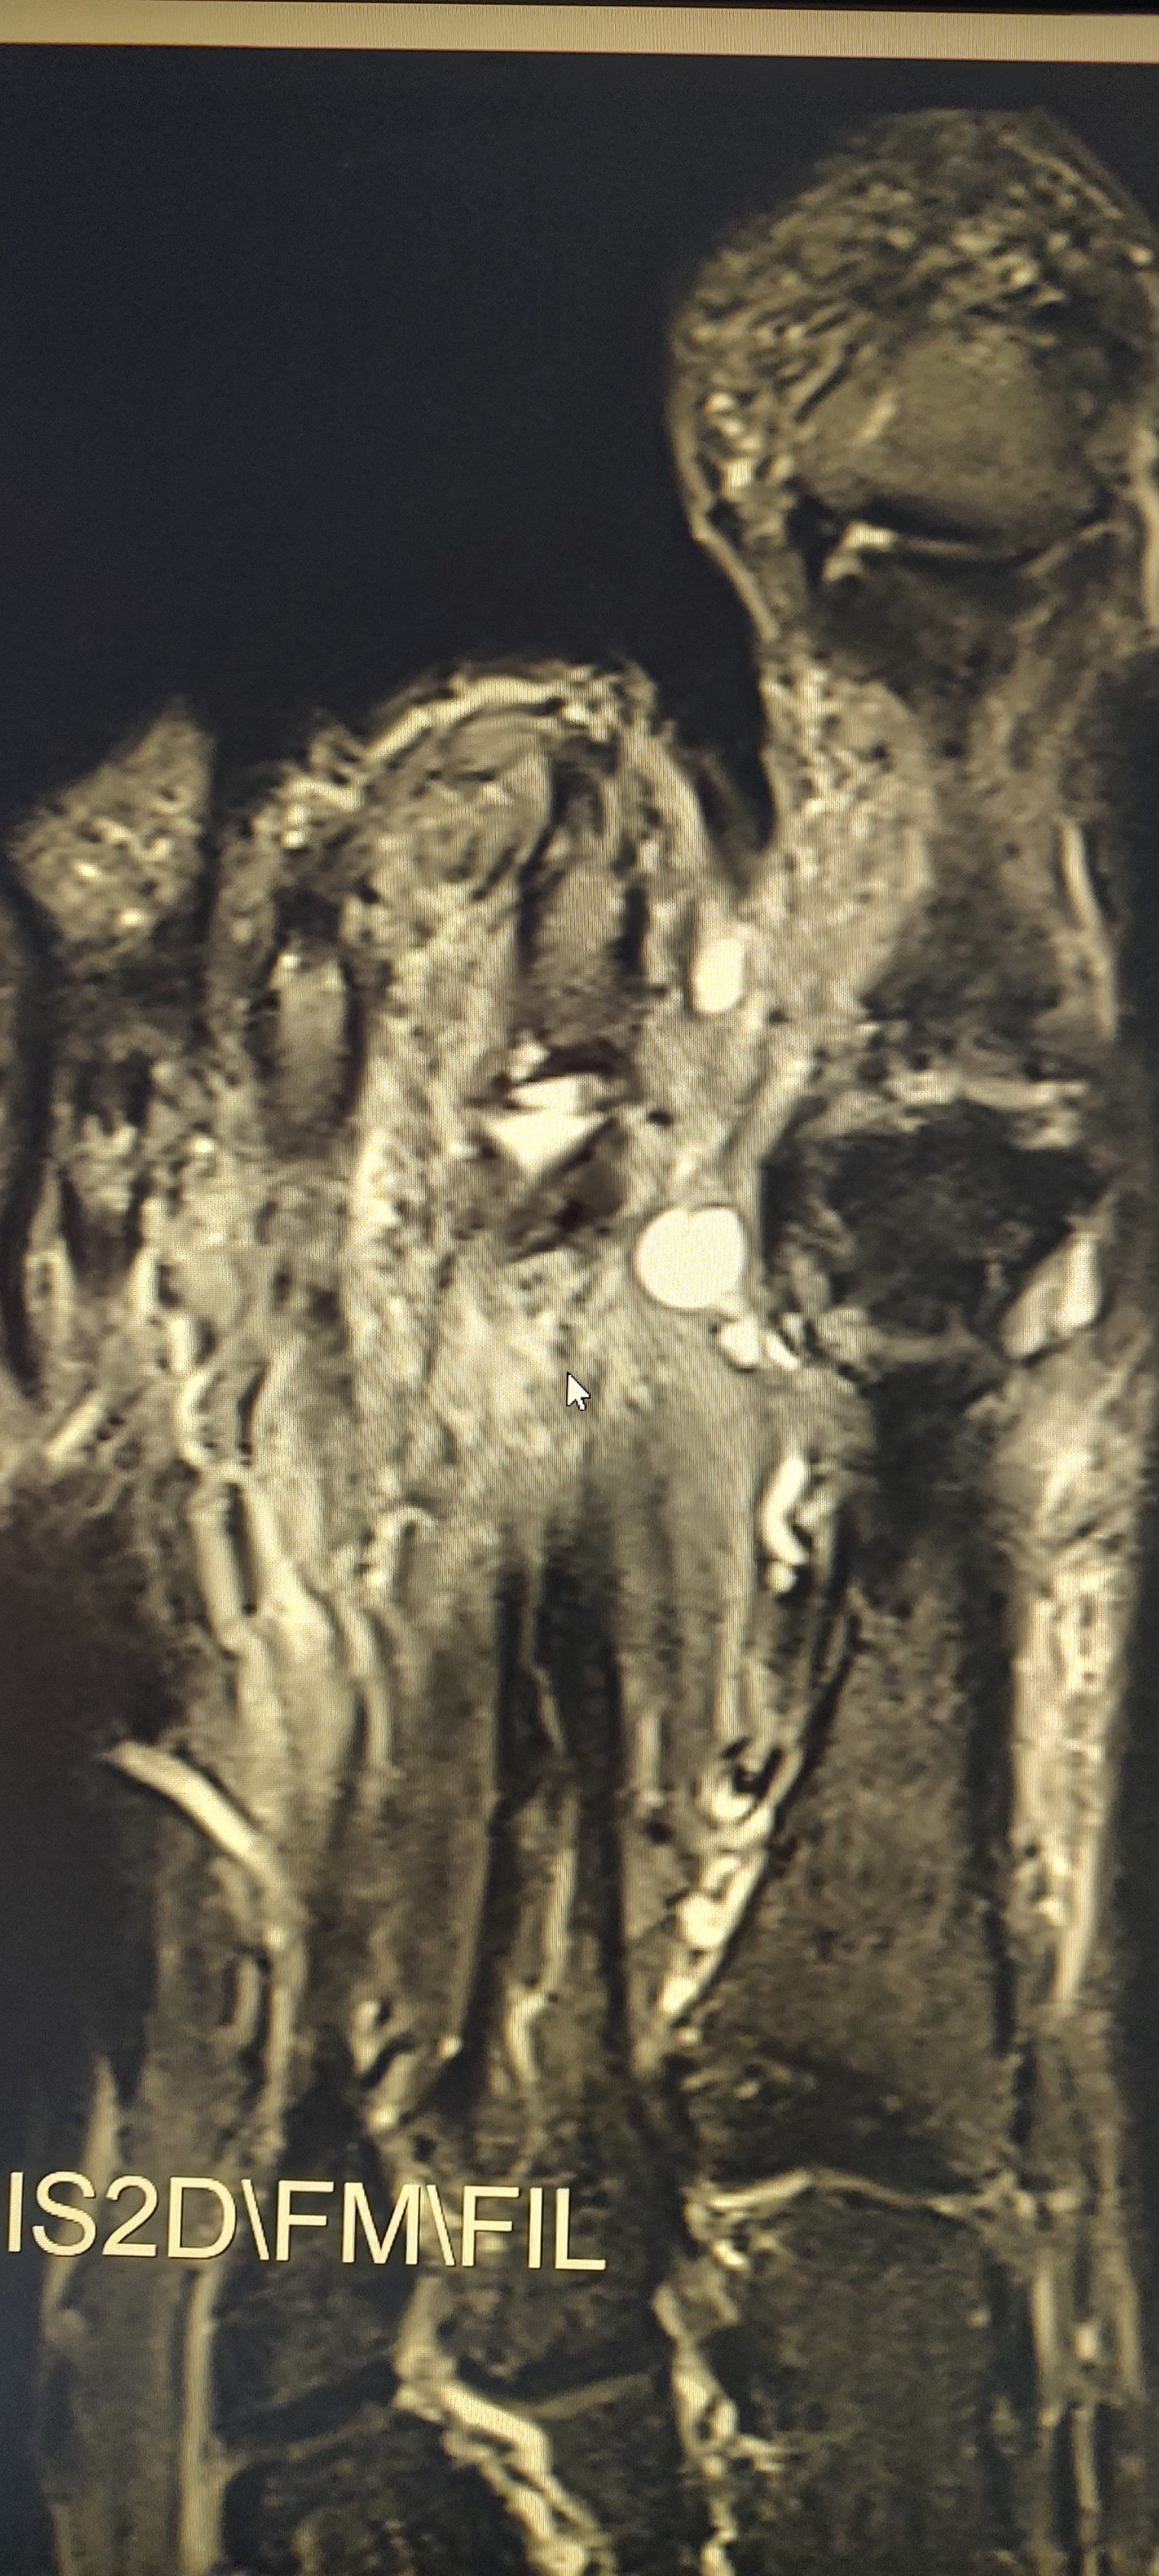

Habe aus dem MRT dieses Bild genommen, ich denke, die weissen Stellen sind die Gewebeansammlungen, die stören. Kennt sich da jemand aus?

8Jetzt ist der Befund aufgetaucht - das Schmerzen verurschende Teil heisst wohl Ganglion, ca 6mm groß. Wird als klein angesehen, keine weiteren Probleme im Fuß ansonsten.